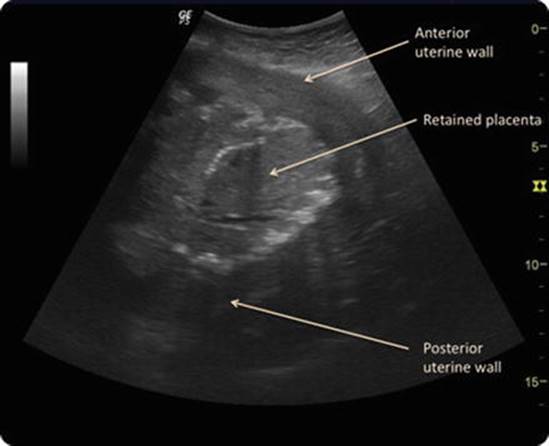

Physical Examination

Patients with significant hemorrhage, particularly those with any vital sign changes including tachycardia, should be taken to the operating room for an exam under anesthesia. The lighting and instruments of an operating room are optimal for this examination and often necessary for adequate repair of deep or complex vaginal or cervical lacerations or to perform a dilation and curettage if needed.In stable patients, request a stretcher or bed with stirrups to facilitate a thorough vaginal exam and repair of any lacerations. An abdominal and bimanual exam should be performed to assess fundal tone and evaluate for any clots or retained placenta. A bedside ultrasound can also be useful when performed by a skilled provider to assess for evidence of retained products of conception (Fig. 12.3). If the uterine fundus is difficult to palpate, ensure the patient’s bladder is empty. A full or distended bladder can hinder uterine contraction as well as make the exam more difficult. In a hemorrhaging or unstable patient, a urinary catheter is indicated for monitoring of output.

Fig. 12.3

Retained placenta. Ultrasound image of retained placenta in situ (Reprinted from Rosenstein and Vargas [27] with permission from Elsevier)

The underlying cause of uterine hemorrhage may be suggested by the patient’s medical history—including known thrombocytopenia or clotting disorders—and is often confirmed by physical examination. Uterine inversion is suggested by depressed fundal height and part of the inverted uterus prolapsing into the vagina. An abnormally adherent placenta should be suspected in patients with a history of uterine surgery or prior placenta accreta or following difficult or piecemeal delivery of the placenta. Atony is suggested by an enlarged, boggy uterus. Uterine rupture should be suspected in patients with fetal bradycardia, abdominal pain independent of contractions, and vaginal bleeding, though hemorrhage may be concealed within the abdomen. Patients with uterine rupture may develop hypovolemic shock; bedside ultrasound may reveal complex free fluid in the abdomen resulting from intra-abdominal hemorrhage [29]. Lacerations are usually visualized by vaginal exam, which should include a thorough assessment of the cervix, vaginal sulci, and periurethral area. A cervical laceration should be suspected if no vaginal laceration is identified and the uterus has appropriate tone, without suggestion of retained products of conception by ultrasound. There is usually insufficient time for a formal ultrasound, but bedside ultrasound can be helpful in diagnosing retained products of conception when performed by an experienced clinician (Fig. 12.3) [27].